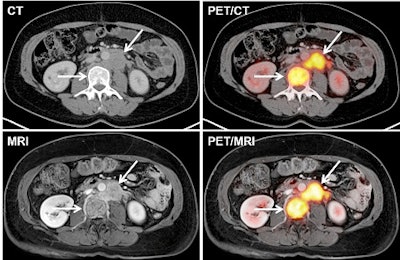

PET/MRI can provide high diagnostic performance for restaging gynecological cancer patients compared with FDG-PET/CT, with only slightly longer scan time and "markedly reduced" radiation exposure, according to a German study published online in the European Journal of Radiology.

PET/MRI has been touted in previous research for its accurate assessment of cancer patients by combining simultaneous whole-body PET with whole-body MRI. MRI's benefits include superior soft-tissue contrast with less ionizing radiation exposure than CT.

In terms of qualitative assessment for visualizing lesions, PET/CT showed significantly higher values for the delineation of lung metastases, while PET/MRI achieved significantly higher lesion-to-background contrast for bone metastases.